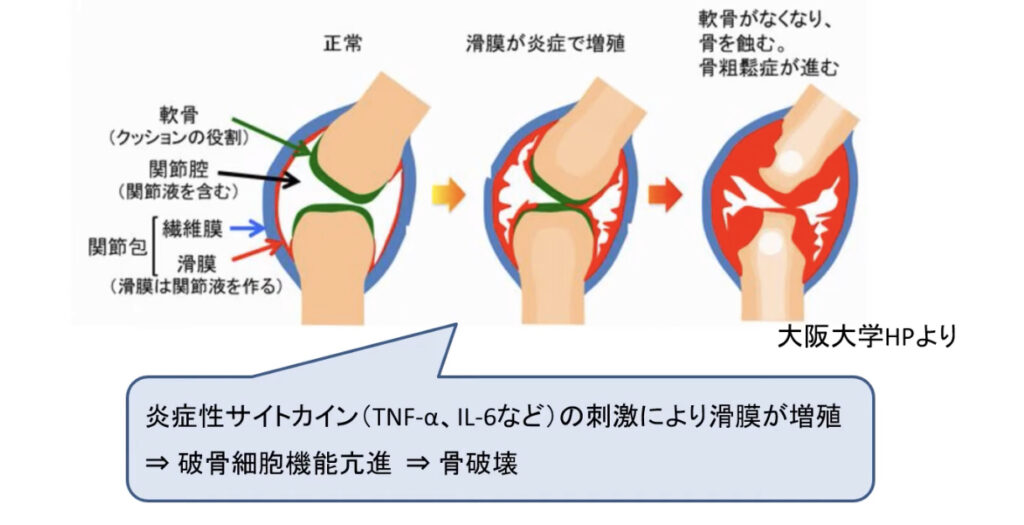

原因は遺伝が40%、環境因子が60%と言われています。環境因子とは感染、けが、妊娠、出産などがあります。免疫系が過剰に働くことにより関節内に炎症が起きて滑膜細胞が増殖し痛みや腫れを起こし軟骨や骨を破壊していきます。

関節リウマチの進行機序

初期は炎症性滑膜炎による痛みと腫れです。進行すると滑膜炎が悪化しパンヌスを形成し軟骨を浸食し骨が破壊され変形性関節症が進みます。通常の変形性関節症と異なるのは関節全体が一様に破壊されてくるため強い変形を来しやすいのが特徴です。

リウマチは自己免疫異常による関節滑膜の増生が主体の病変であるため、免疫抑制剤による全身療法が基本となります。